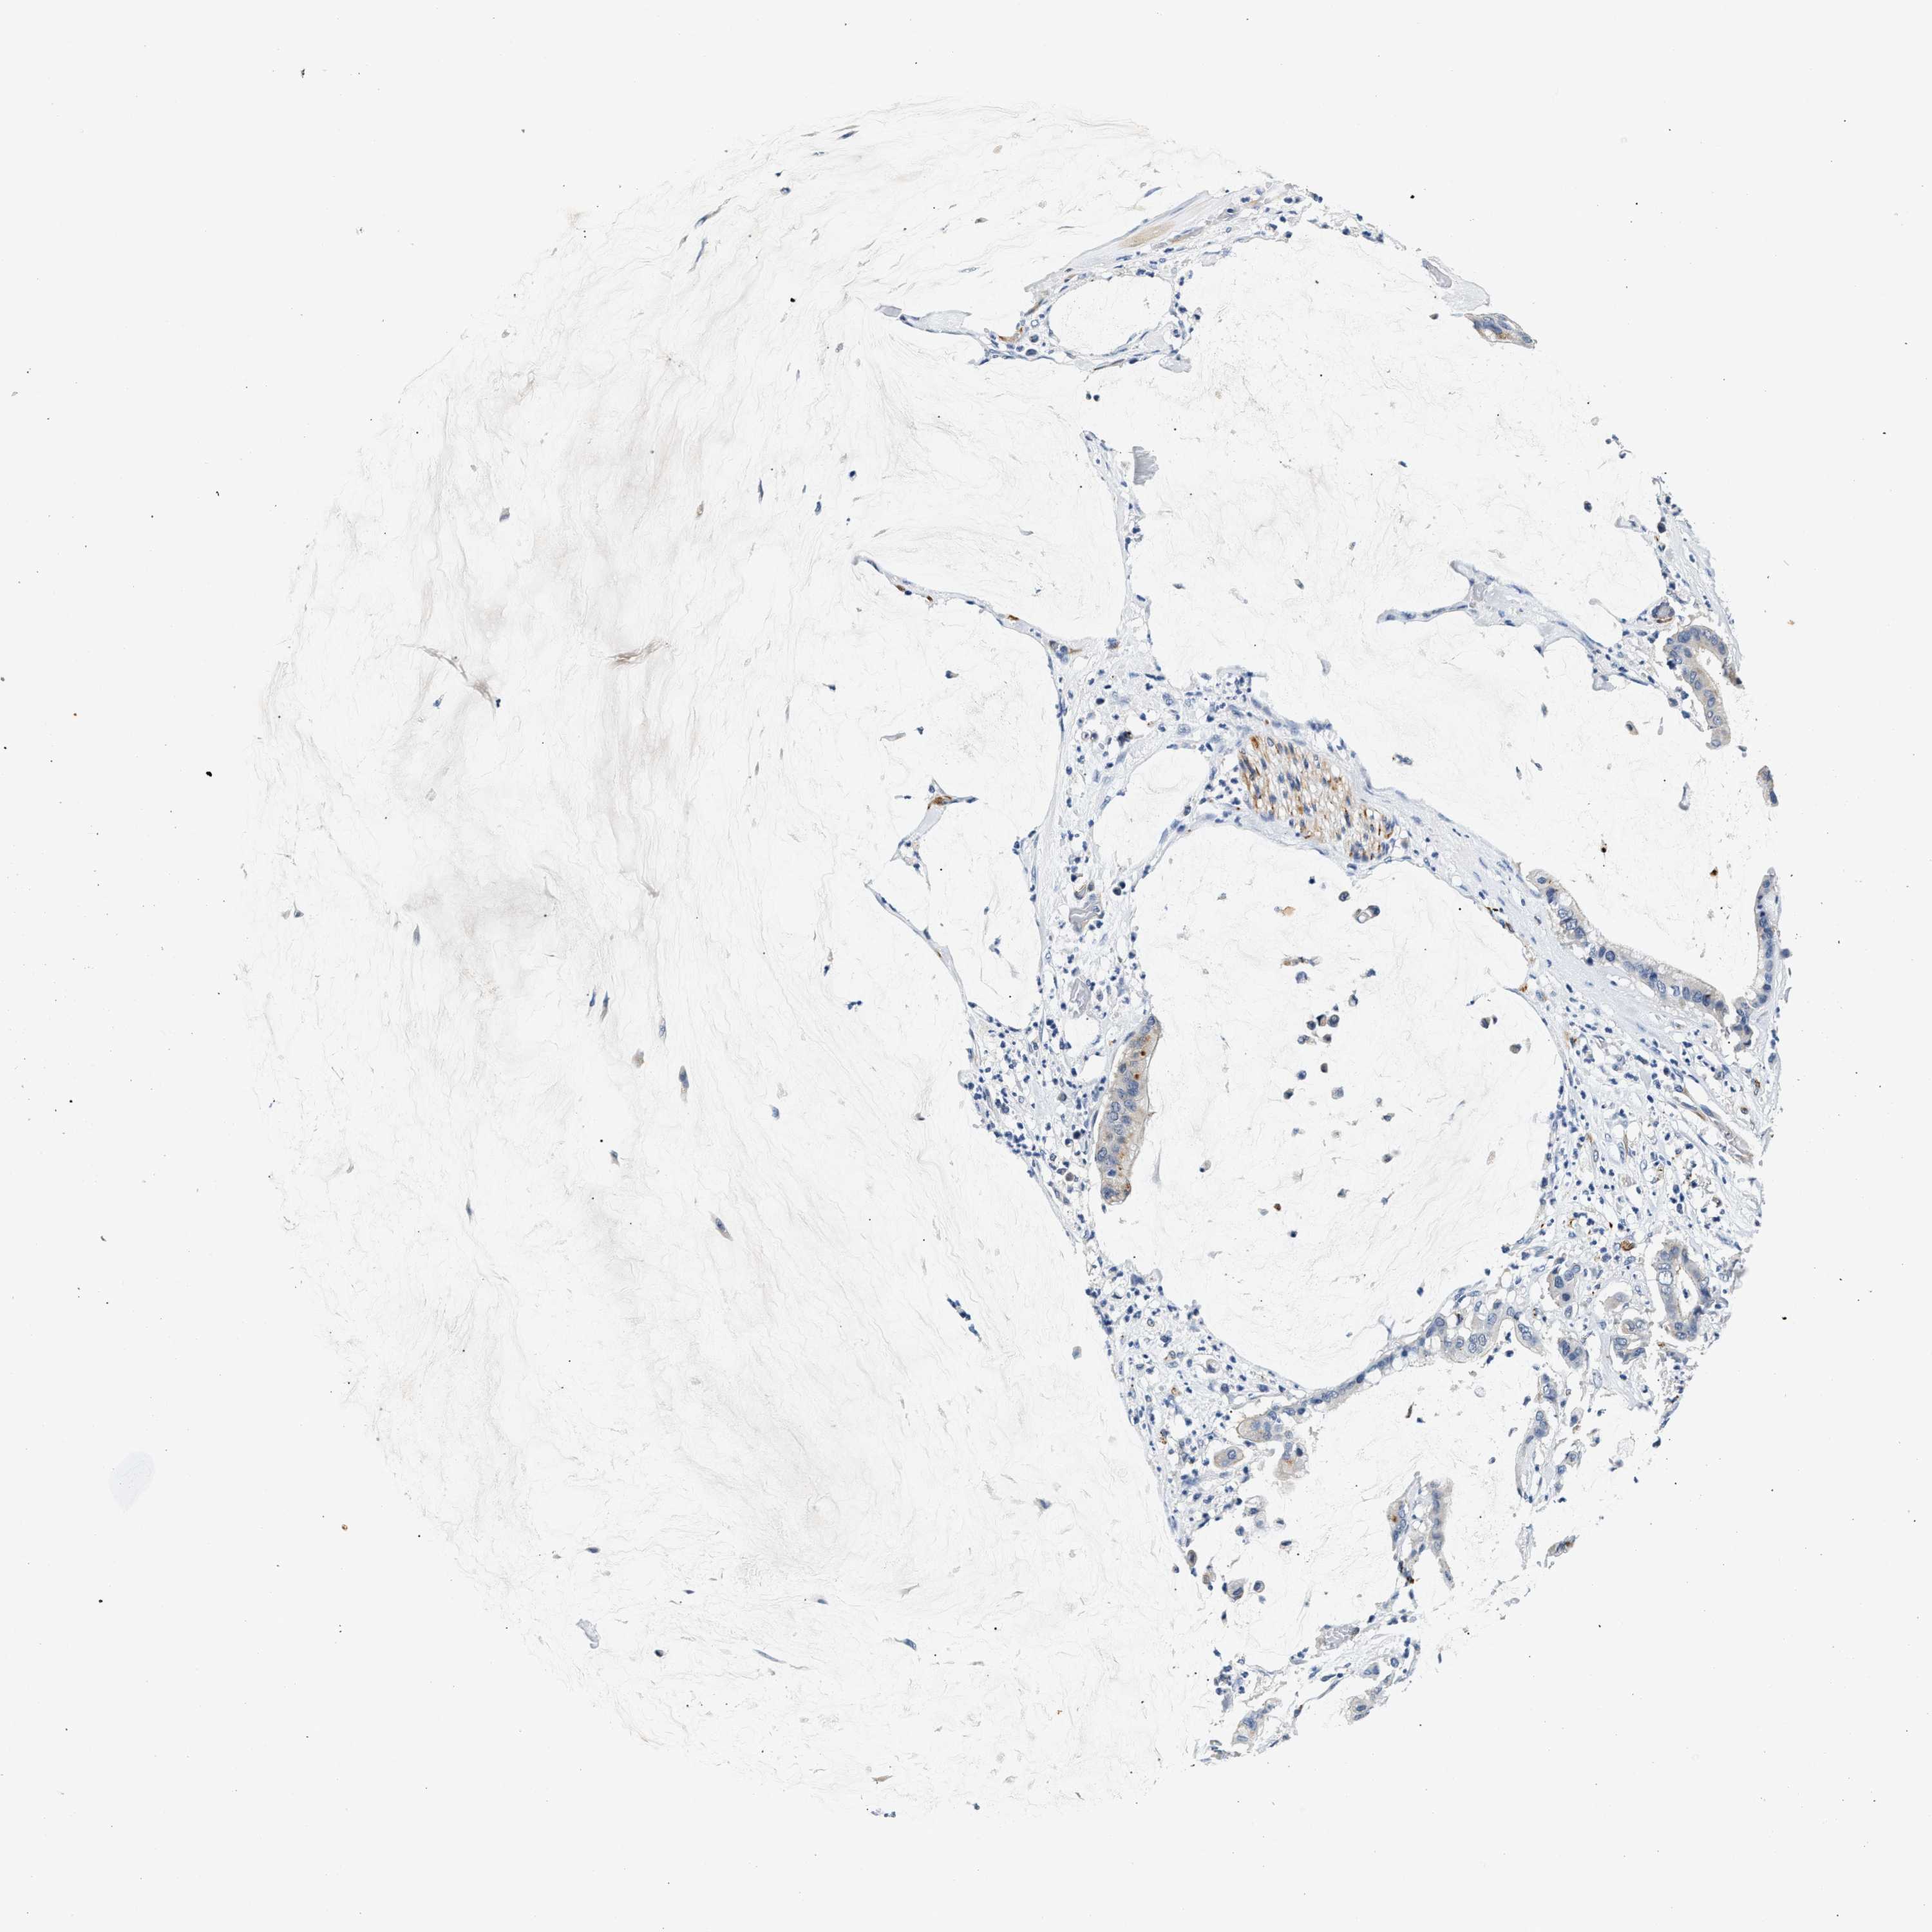

PANCREATIC CANCER - Protein expressioni

A mouse-over function shows sample information and annotation data. Click on an image to view it in a full screen mode. Samples can be filtered based on level of antibody staining by selecting one or several of the following categories: high, medium, low and not detected. The assay and annotation is described here.

Note that samples used for immunohistochemistry by the Human Protein Atlas do not correspond to samples in the TCGA dataset.

Antibody stainingi

Antibody staining in the annotated cell types in the current human tissue is reported as not detected, low, medium, or high, based on conventional immunohistochemistry profiling in selected tissues. This score is based on the combination of the staining intensity and fraction of stained cells.

Each image is clickable and will lead to virtual microscopy that enables deeper exploration of all samples and also displays staining intensity scores, fraction scores and subcellular localization as well as patient and tissue information for each sample.

Antibody HPA020391

Staining

High

Medium

Low

Not detected

Intensity

Strong

Moderate

Weak

Negative

Quantity

>75%

75%-25%

<25%

None

Location

Nuclear

Cytoplasmic/membranous

Cytoplasmic/membranous,nuclear

Adenocarcinoma, NOS